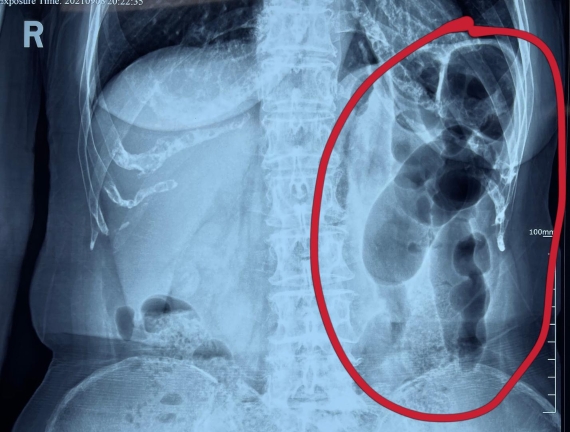

據(jù)省醫(yī)院消化病院消化二科姜子曄醫(yī)生介紹,韓大娘今年已經(jīng)73歲,家住哈爾濱市,一周前開始腹脹腹痛,有較為明顯的左側(cè)腹部疼痛,疼痛劇烈時會出現(xiàn)左側(cè)腹部鼓包情況,排氣排便后有所好轉(zhuǎn)。韓大娘家人見狀將其送到了黑龍江省醫(yī)院,門診檢查腹部平片提示為左側(cè)腹部積氣,口服全消化動力藥及通便治療后腹痛腹脹有所緩解,入院前再次突發(fā)左側(cè)腹痛加重伴有明顯腹脹,急診隨后以“腹痛腹脹原因待查”將韓大娘收入到消化病院消化二科。

姜子曄醫(yī)生熱情接待了韓大娘,為其進(jìn)行了仔細(xì)查體,除了左側(cè)腹部壓痛并未見明顯異常,對癥給予灌腸后,韓大娘的腹脹有所緩解,第二天姜子曄醫(yī)生為韓女士進(jìn)行了胃腸鏡檢查,也未見明顯異常。但此時韓大娘腹部平片結(jié)腸腸管擴(kuò)張仍然很嚴(yán)重,腹痛腹痛也沒緩解,到底什么原因呢?消化二科主任陸以霞在查房時建議繼續(xù)給予韓大娘口服全消化動力藥,必要時灌腸治療,同時陸以霞主任在追問病史查體時發(fā)現(xiàn)韓大娘左下腹紅色皮疹和小水泡,反復(fù)抓撓腹部皮膚部分已結(jié)痂,高度懷疑為帶狀皰疹。